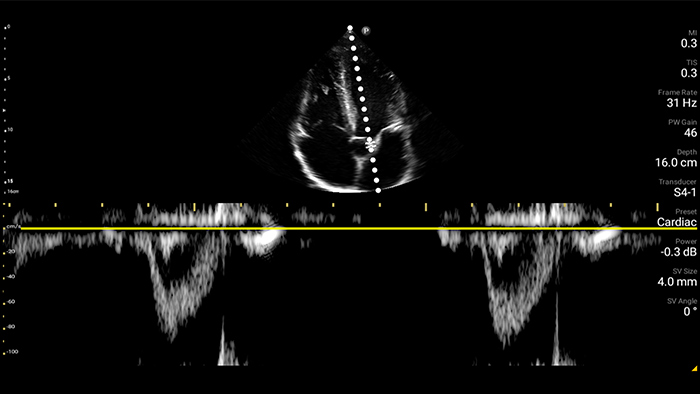

Actúe más rápido para proteger el corazón de sus pacientes

Cuando los segundos cuentan, el ultrasonido portátil puede marcar la diferencia. Lumify puede proporcionar las imágenes de alta definición que requiere cuando y donde las necesite.

Oportunidad de revertir potencialmente la miocardiopatía

Introducción a la ecocardiografía transtorácica